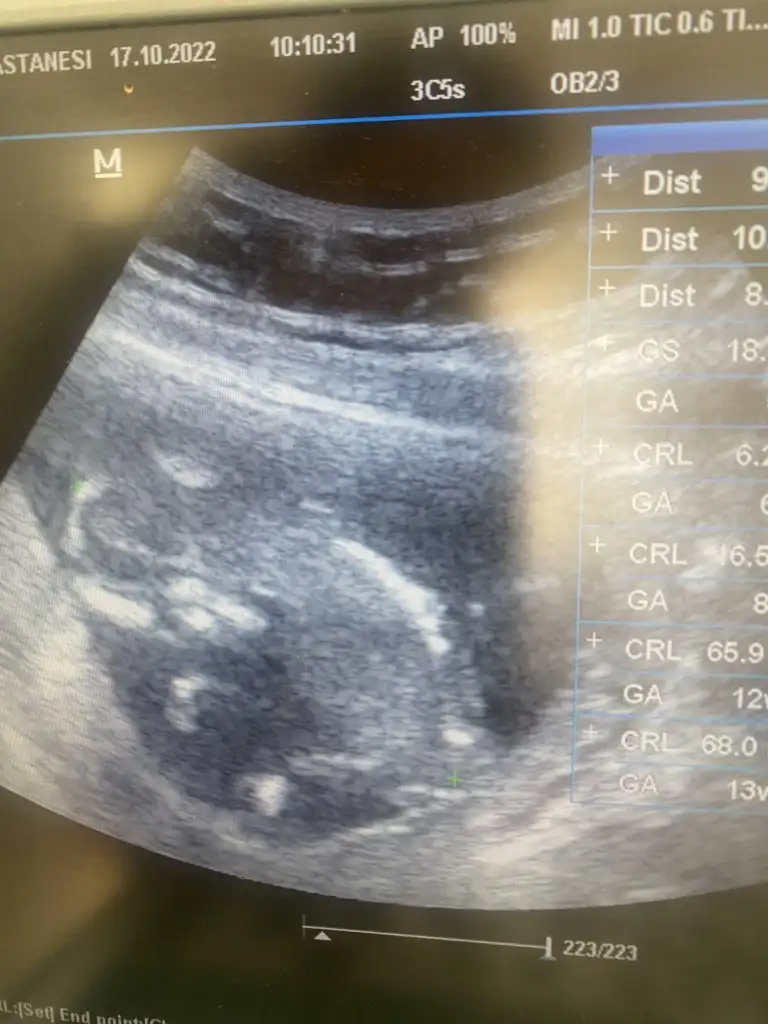

Cinsiyetten hiç anlamıyorum ama Allah sağlıkla kucağına almayı nasip etsin canimkızlar varmı bana tahmini olanbizim tüp bebek oldğu için valla bi gisiydiyorm doktor diyor 12+2 bugun gittim 13+4 diyo sürekli değişiyor cinsiyet tahmininiz varmı acaba

Ultrason dan ultrasonada değişiyor canım yada geride olup haftasını yakalıyorlar öne geçiyorlar tahmini ölçümler olduğu için değişebiliyor hepamiin inşallah hepimiiiizihayırlı sağlıklı olsunda kızımda yok oğlumda ama insan merak ediyor ya aslında benim sat 13 temmuz peritlg 22 temmuz diyor takipte oldğum doktor ise 17 temmuz dedi hepsi farklı bir hesap söylüyor takipte oldğum doktora göre suan 13+5 gzöüküyor

Bizimkinin cinsiyeti çok erken ortaya çıktı 12. haftada tahmin yapmıştı doktorumuz, 13. haftada netleşti, genetik testle de kesinleştirmiş olduk.